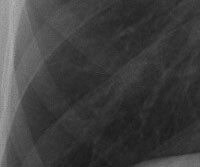

Røntgenbilde av en lunge med silikose

Lunge med silikose